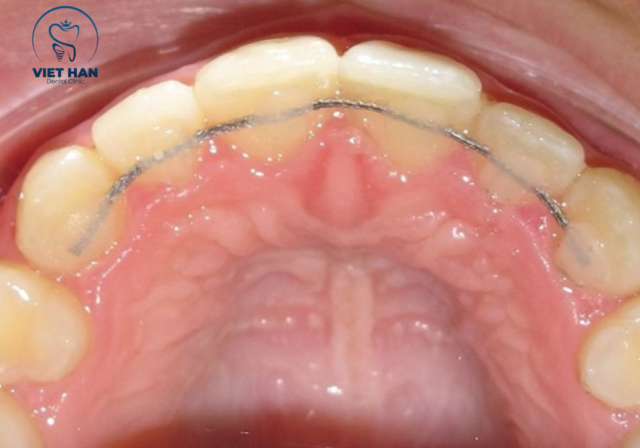

1. Hàm duy trì cố định

Hàm duy trì cố định thường là một đoạn dây kim loại mảnh được gắn vào mặt trong răng bằng vật liệu composite. Loại hàm này giúp giữ răng ổn định liên tục 24/7 nên hạn chế tối đa nguy cơ quên đeo. Đồng thời, vì nằm ở mặt trong nên gần như không ảnh hưởng đến thẩm mỹ khi giao tiếp.

Hàm duy trì cố định gắn mặt trong răng giúp giữ răng ổn định liên tục.

Tuy nhiên, nhược điểm là khó vệ sinh hơn so với các loại tháo lắp. Nếu không chăm sóc răng miệng kỹ, mảng bám có thể tích tụ gây sâu kẽ hoặc viêm nướu. Ngoài ra, không phải trường hợp nào cũng có thể áp dụng hàm cố định vì còn phụ thuộc vào khớp cắn của từng người.